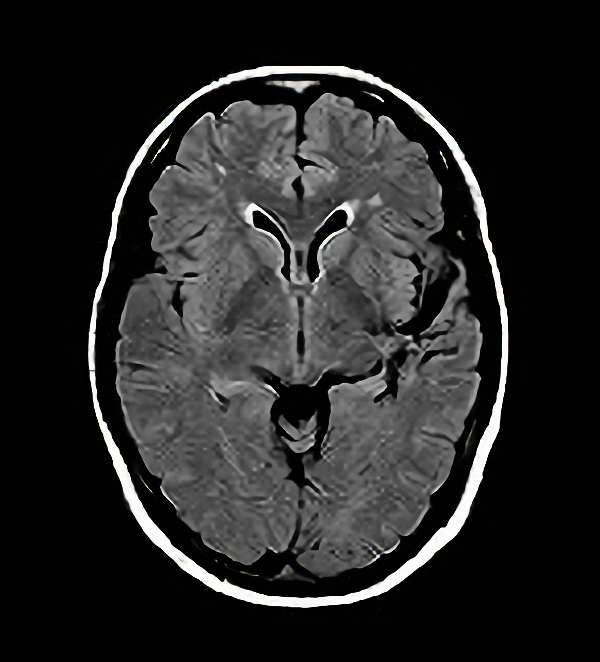

No.452 手術前